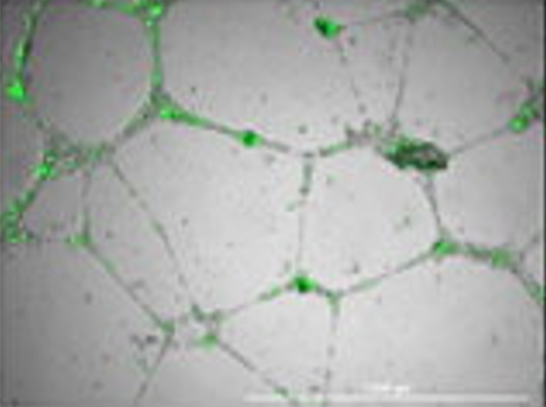

3-D Angiogenesis Model - Cells in 3-D Culture.

Our 3-D Tissue Like Models are proving excellent for drug discovery. For example, our 3-D Blood Brain Barrier Models is being used to test the ability of compounds, molecules and oligos to pass through the blood barrier and penetrate the brain side of the model.